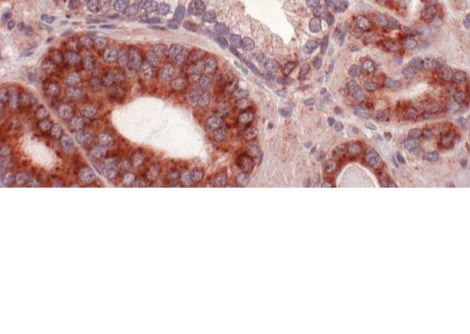

أدلة من تحليل خلايا الجلد

في دراستهم، فحص الباحثون السجلات الطبية لأكثر من 32,000 مريض بأمراض جلدية، بما في ذلك استخدامهم لأجهزة تسمير البشرة، وتاريخ إصابتهم بحروق الشمس، والتاريخ العائلي للإصابة بسرطان الجلد. كما حصلوا على عينات جلدية من 26 متبرعاً، وقاموا بتحليل تسلسل 182 خلية.

أظهرت النتائج أن مستخدمي أجهزة تسمير البشرة من الشباب لديهم طفرات جلدية أكثر من الأشخاص الذين يكبرونهم بضعف أعمارهم، وخاصة في أسفل الظهر، وهي منطقة لا تتعرض لأضرار كبيرة من أشعة الشمس، ولكنها تتعرض بشكل كبير من أجهزة تسمير البشرة.

قال المؤلف الرئيسي للدراسة، الدكتور أ. هنتر شاين، الأستاذ المشارك في قسم الأمراض الجلدية بجامعة كاليفورنيا في سان فرانسيسكو: "كانت بشرة مستخدمي أجهزة التسمير مليئة ببذور السرطان - خلايا تحمل طفرات معروفة بأنها تؤدي إلى سرطان الجلد الميلانيني".